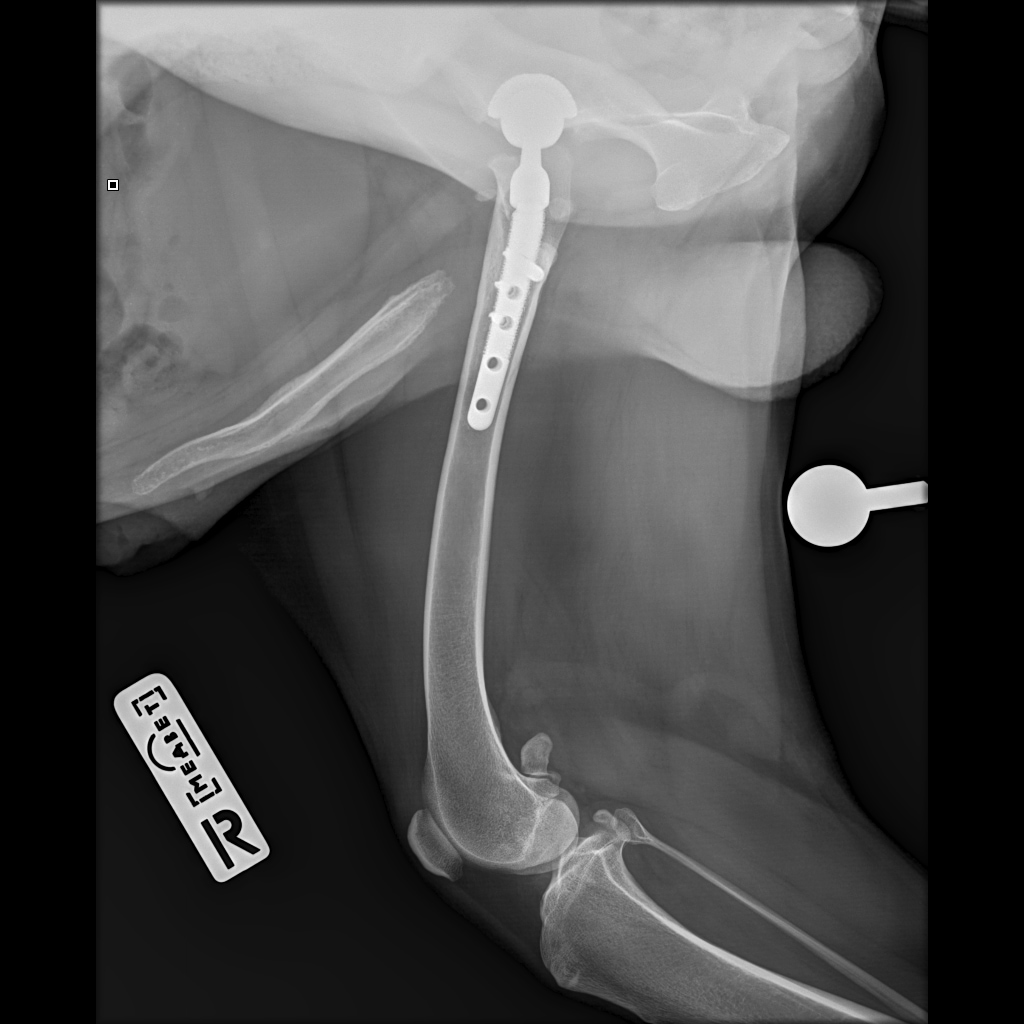

F37B4905-A77F-43B7-A3A7-4AAD9E739F82.jpeg

E6A744CC-768F-480D-8917-7FDAD53F05BD.jpeg

DA1A1524-BA63-434B-95BE-C121F7D5334F.jpeg

4D4A6426-4FE5-4417-ACCB-6DE53B57B90E.jpeg

E358D56E-67BF-4D4C-B3F0-BF8F4089D7A2.jpeg

767DD36C-E2E2-41FB-9CCF-6940421D2BB2.jpeg

701487DA-D6D9-4CE0-B18B-EEB120E78EF2.jpeg

Мы ничего не оплачивали. Все включено.

За время противовоспалительной терапии снизилось воспаление и в левом тазобедренном суставе, но увы, форма головки бедренной кости и состояние шейки бедра , лучше не стали:(((

Операция однозначно нужна.

Снимки столь качественные, что их можно в учебник